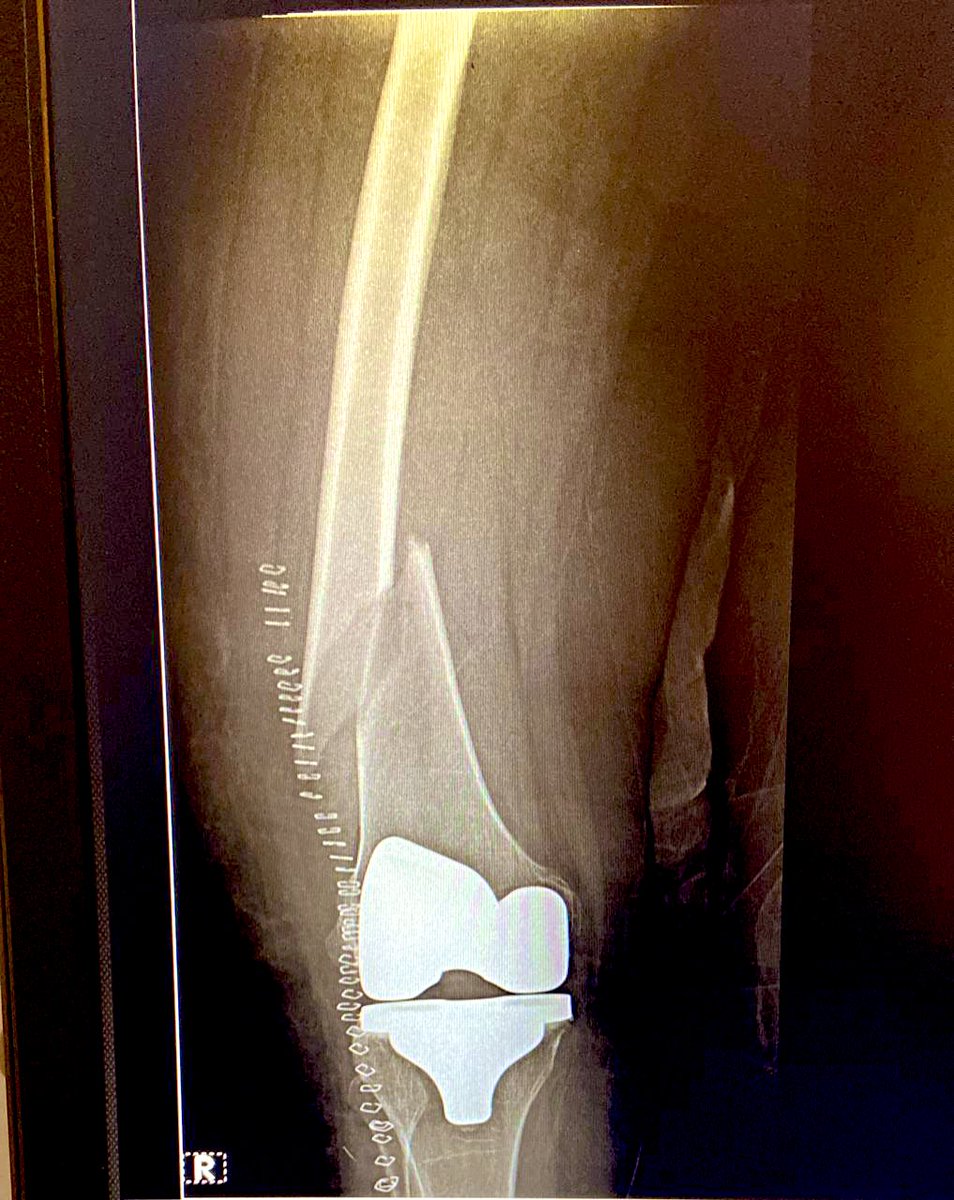

Her X Ray showed fracture inches above TKR

In fifty days this was the status. We allowed partial weight bearing but told her not to move around a lot.

Exactly 80 days after her fracture & fixation we took another X Ray.

It showed good recovery, increasing bone density & some micro trabecular patterns.